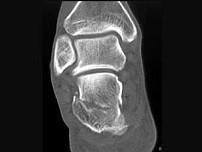

男,36岁,从高处摔下,足部受伤,结合图像,最可能的诊断是?(?)A.距骨骨折B.跟骨骨折C.骰骨骨折D.舟状骨骨折E.楔骨骨折

问题 男,36岁,从高处摔下,足部受伤,结合图像,最可能的诊断是?(?)

选项 A.距骨骨折 B.跟骨骨折 C.骰骨骨折 D.舟状骨骨折 E.楔骨骨折

答案 B